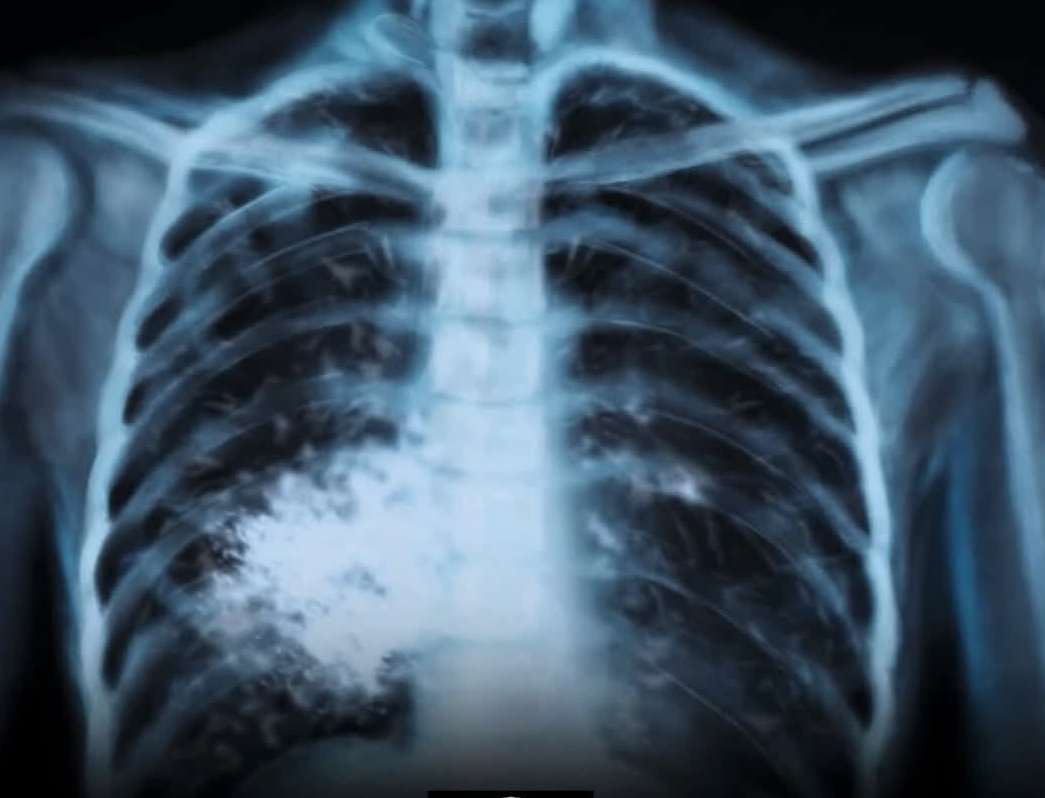

ЦИГАРИТЕ СА ПРОДУКТ, КОЙТО УБИВА ПОЛОВИНАТА ОТ СВОИТЕ ПОТРЕБИТЕЛИ

Ако някога моралът на политици и законотворци в областта на здравеопазването у нас се издигне на национално отговорна висота, а хората разберат, че собственото им здраве зависи от техния личен избор на поведение, тогава може би производителите на тютюневи изделия ще бъдат притиснати в ъгъла и принудени да се откажат от ролята на змията-изкусителка, която изобретява все нови и нови видове тютюневи “ябълки”, с които съблазнява все нови и нови наивници, които вярват, че това е пътя на израстването, знак за независимост и зрялост. Така неусетно желанието им да бъдат забелязани, да бъдат харесани, да станат влиятелни и значими сред тези, с които общуват, ги отвежда не до рая, а до ада на употребяващите никотин. Защото наистина няма значение дали пушиш традиционни или електронни цигари, вейпове, наргилета, бездимни или такива, които си свиваш сам. Един ден собственото ти тяло ще те изправи пред нечий лекарски кабинет.